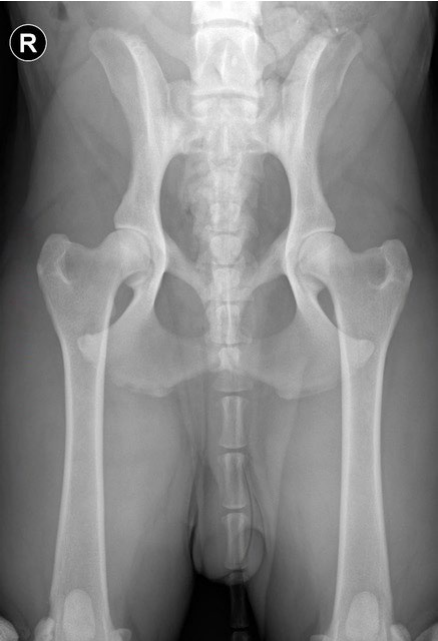

Hips

- A single extended VD view of the pelvis is required for scoring, taken under general anaesthetic or heavy sedation, to enable correct positioning.

- The dog is positioned in dorsal recumbency and the hind limbs extended caudally

- The image should include the wings of the ilia cranially, and if possible, include the stifles (if the size of the dog allows). Priority should be given to including the wings of the ilia rather than the stifles if the dog is too large.

- The x-ray beam is centred over the hips, this can be achieved by palpating bony landmarks such as the cranial edge of the pubic symphysis, and the greater trochanters.

- The femurs are held parallel by rotating the limbs medially, so that the patellas are superimposed over the distal femurs, and adducting the limbs.

- It is important that there is no tilting or rotation of the pelvis, as this can make one hip look beter and the other look worse than it actually is, affecting the scoring. This can be assessed by checking the wings of the ilia, which should look identical; if there is tilting, one iliac wing will look wider than the other, the wider one being tilted down. Also, the obturator foramina should look identical. A well-positioned pelvis looks symmetrical.